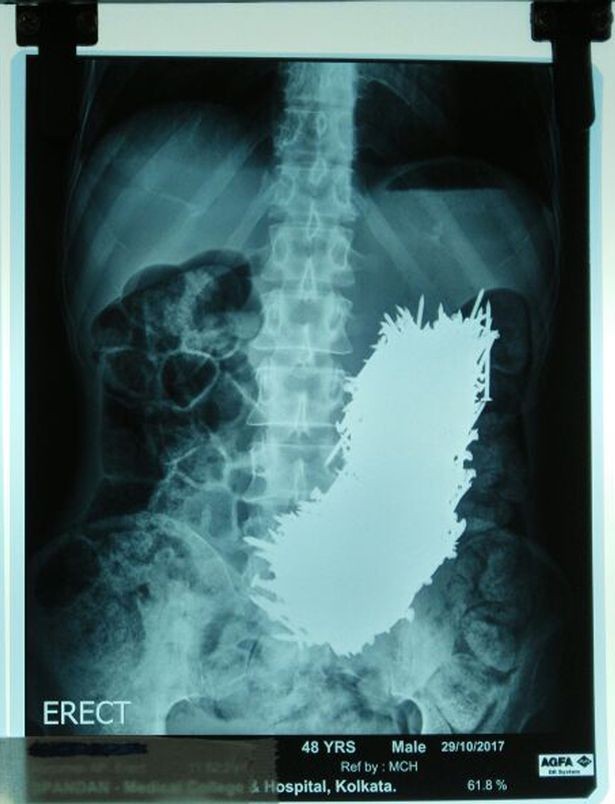

Ảnh chụp cho thấy số đinh khổng lồ trong bụng Pradip |

Các bác sĩ đã sốc khi thấy ảnh chụp siêu âm với tổng cộng 600 đinh sắt trong bụng. Sau 2 ngày quan sát, họ quyết định dùng nam châm trong quá trình phẫu thuật, hút đinh sắt ra khỏi bụng bệnh nhân. Rất may là không có chiếc đinh nào làm thủng dạ dày của ông.

Siddhartha Biswas, bác sĩ đứng đầu cuộc phẫu thuật, cho biết: "Tháng trước, gia đình bệnh nhân đưa cho chúng tôi xem ảnh siêu âm, tôi đã sốc khi thấy đinh trong bụng ông ấy.

"Chúng tôi quyết định phẫu thuật. Điều này rất nguy hiểm vì bụng của ông đã phình to lạ thường và chứa đầy đinh. Nhưng rất may không có cái đinh nào xuyên thủng dạ dày.

"Chúng tôi cắt một phần dạ dày của bệnh nhân và dùng nam châm để lấy đinh ra, từng cái một. Có hơn 600 đinh trong đó. Chúng tôi phải đảm bảo tất cả đinh ông nuốt phải được lấy ra."